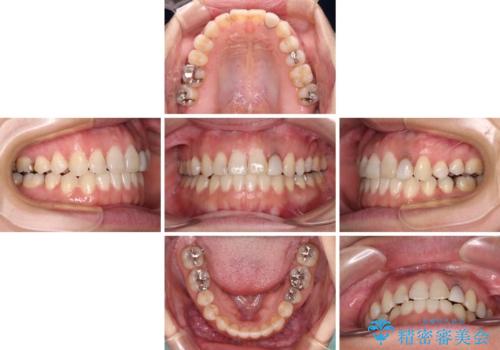

開咬と変色した前歯 インビザライン矯正とオールセラミッククラウン治療

- 前歯の開咬と失活により変色した前歯を気にして来院された患者様です。

開咬の治療は、前歯を閉じるように引っ張り出すよりも、上下臼歯を圧下(骨内にめり込ませる)させることで進める方が長期的に安定した歯列を維持できます。

インビザラインは臼歯の圧下を効果的に行えるため、インビザラインを用いて矯正治療を行うこととしました。

矯正治療が概ね終了した時点で前歯をオールセラミッククラウンにて補綴治療を行い、その後インビザラインにて細かい部分を仕上げていくことしました。